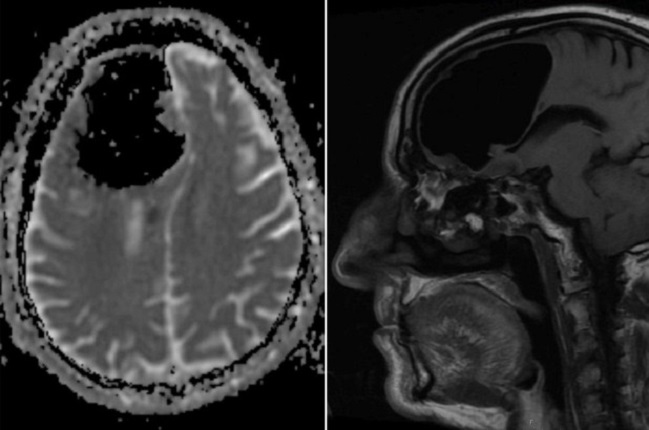

Un hombre de 84 años sorprendió a un grupo de médicos que hallaron un gran hueco de aire en el lugar donde debería ir su cerebro.

Según informó Washington Post, el espacio anormal medía cerca de nueve centímetros y es algo común en pacientes que han tenido cirugía cerebral, aunque en tamaños mucho menores. El fenómeno también podría producirse por infecciones nasales o por golpes faciales.

No fue hasta que le realizaron tomografías cuando notaron el hueco de aire en el lóbulo frontal derecho de su cabeza: una parte de su cerebro estaba desaparecida.